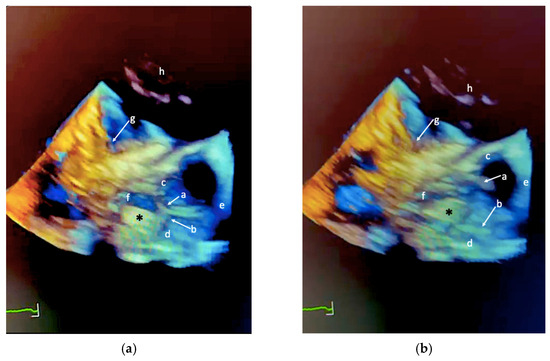

Review

Echocardiographic Assessment of Patients Undergoing Mitral Valve Repair

by Marco Rolando, Nadeem Elmasry, Federico Gobbi, Antonella Moreo, Nina Ajmone Marsan, Erberto Carluccio and Federico Fortuni

J. Cardiovasc. Dev. Dis. 2025, 12(12), 498; https://doi.org/10.3390/jcdd12120498 - 17 Dec 2025

Cited by 1 | Viewed by 1065

Mitral regurgitation (MR) is one of the most prevalent valvular disorders worldwide, with a growing burden driven by population aging and improved diagnostic capabilities. Understanding the mechanism of MR, whether primary, due to intrinsic valve abnormalities, or secondary, resulting from atrial or ventricular [...] Read more.

Mitral regurgitation (MR) is one of the most prevalent valvular disorders worldwide, with a growing burden driven by population aging and improved diagnostic capabilities. Understanding the mechanism of MR, whether primary, due to intrinsic valve abnormalities, or secondary, resulting from atrial or ventricular remodeling, is essential for optimal management. Echocardiography, particularly advanced modalities such as three-dimensional imaging and strain analysis, plays a central role in this process. It allows accurate quantification of MR severity, detailed characterization of valve and ventricular anatomy, and assessment of remodeling, all of which are critical for determining the optimal timing for intervention. Beyond diagnosis, echocardiography is indispensable in guiding therapy selection: it informs surgical planning by defining leaflet pathology for repair versus replacement strategies, and directs transcatheter interventions by guiding interatrial septal puncture, catheter orientation, and device deployment in real time. While surgery remains the gold standard for primary MR, transcatheter approaches including edge-to-edge repair and emerging mitral valve replacement are increasingly relevant, particularly in patients at high surgical risk or with complex anatomy. This review emphasizes the pivotal role of echocardiography in the pre-procedural assessment of MR, highlighting its ability to integrate anatomical, functional, and hemodynamic information to guide patient-tailored therapeutic strategies and optimize outcomes within a Heart Team framework. Full article

Show Figures

Figure 1